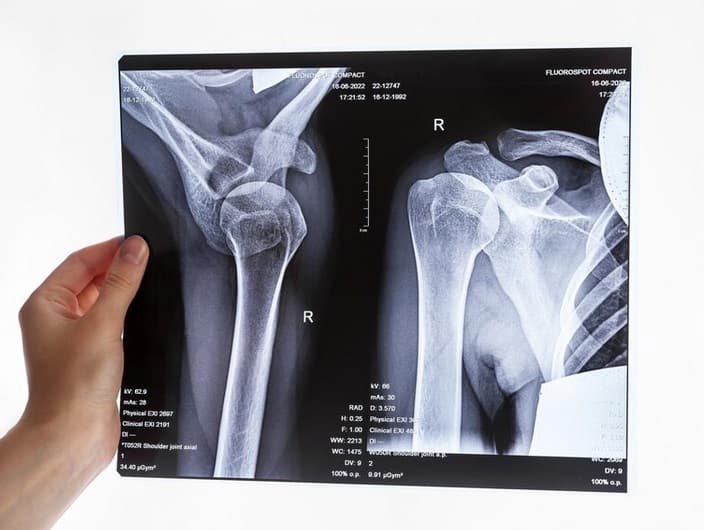

• جراحی شانه و آرنج ها

• آرتروسکوپی مفاصل در آن جراحی ارتوپد بوسیله سوراخ ریزی بر روی پوست مفصلی ایجاد میکنند لوله ای را به داخل مفصل فرستاده و درون مفصل را میبینند. از این کار برای تشخیص دادن بیماری مفصلی و درمان برخی از آن هااستفاده میشود.